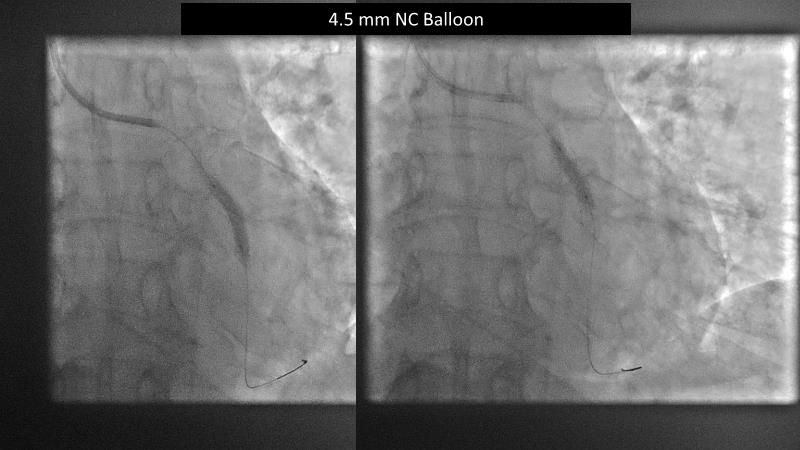

Watch this session to gain case-based insights on using DCBs in complex settings. Learn valuable tips and tricks for optimal DCB application, including the best timing and situations for their use. Discover how to effectively implement a hybrid strategy that combines DES and DCB when needed.

- To get a case based experience on how to use a DCB in complex settings

- To learn about tips and tricks on how and when to use a DCB: the ideal time and situation of DCB application in various complexities

- To utilise the hybrid strategy approach Combining DES and DCB when the situation demands